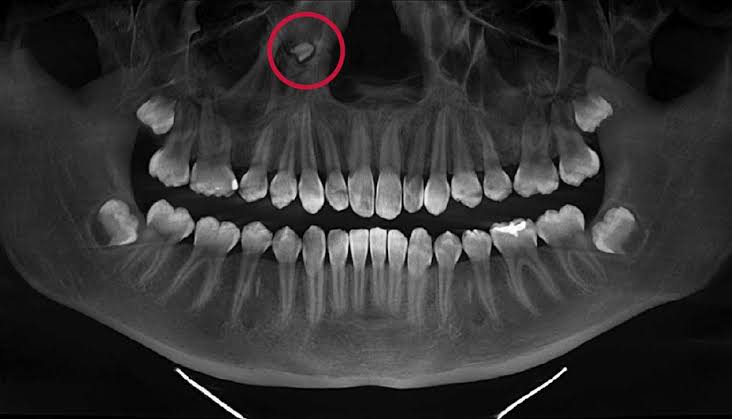

3. ECTOPIC TEETH

A 38-year-old male patient complaining of difficulty breathing through one of his nostrils for several years was found to have an ectopic tooth growing in his nose. They are body parts growing in places where they normally do not grow.